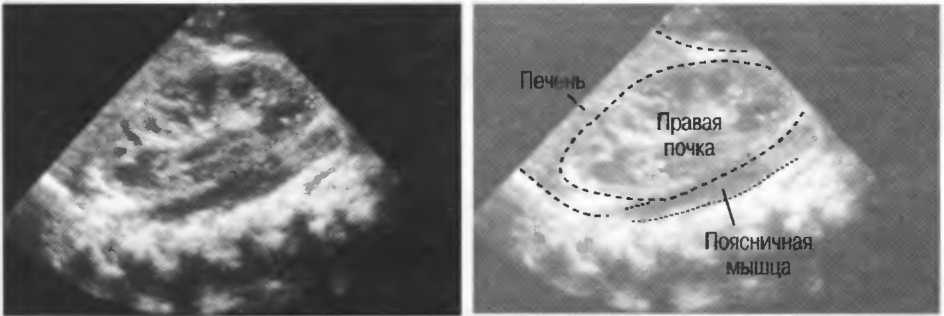

4. У здоровых обследуемых паренхима печени должна быть немного более эхогенна. чем кора рядом расположенной почки (рис. 26).

Рис.26. Продольный срез через печень и правую почку: нормальная паренхима печени более эхогенна, чем паренхима нормальной почки. Это еще один способ проверки качества изображения.